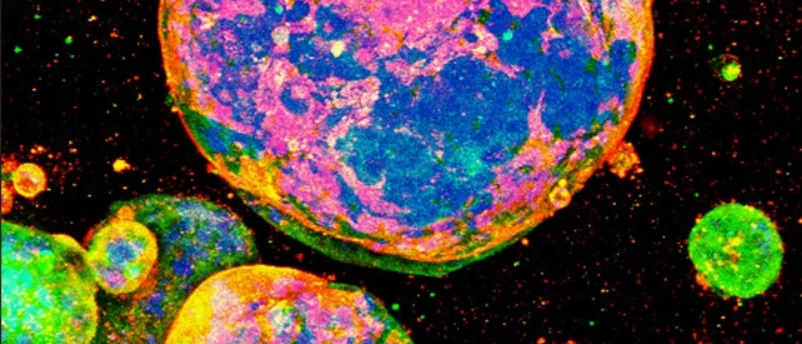

In a significant advancement poised to reshape the landscape of pharmaceutical development, a collaborative team from ETH Zürich and the…

A pioneering team of researchers from ETH Zurich and Karolinska Institutet has unveiled a groundbreaking cross-linking MALDI mass spectrometry (MS)…

A groundbreaking development from a collaborative team at ETH Zurich and Karolinska Institutet promises to revolutionize early-stage drug discovery by…

A groundbreaking advance in drug discovery, developed by a collaborative team from ETH Zürich and Karolinska Institutet, promises to significantly…

A groundbreaking collaborative effort between researchers at ETH Zurich and Karolinska Institutet has culminated in the development of a novel…